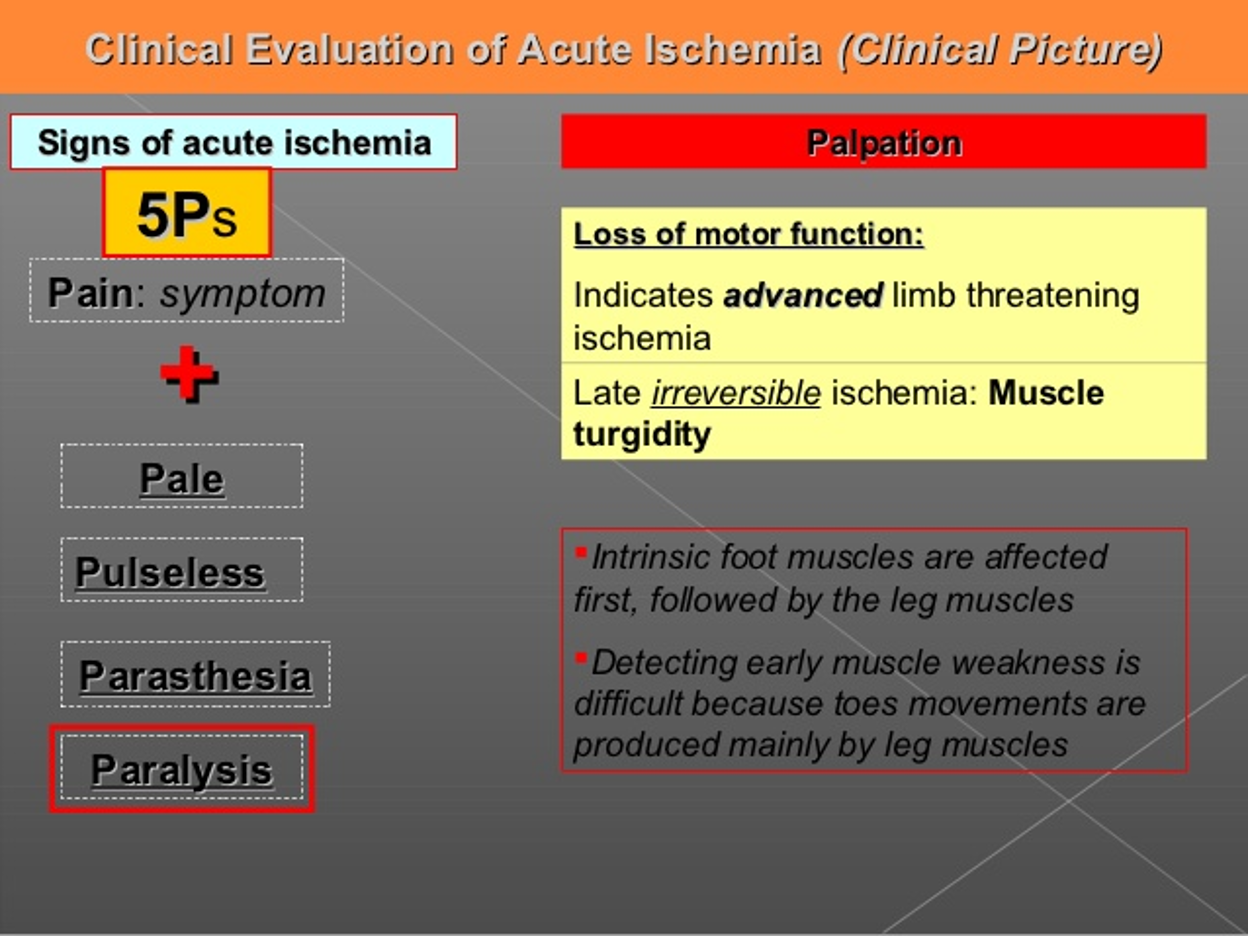

- Paralysis